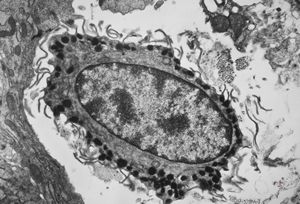

M, 3y. | cutaneous nerve